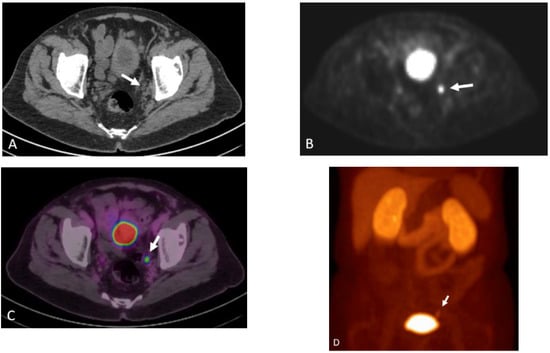

Detection of Loco-Regional Disease and Distant Metastases